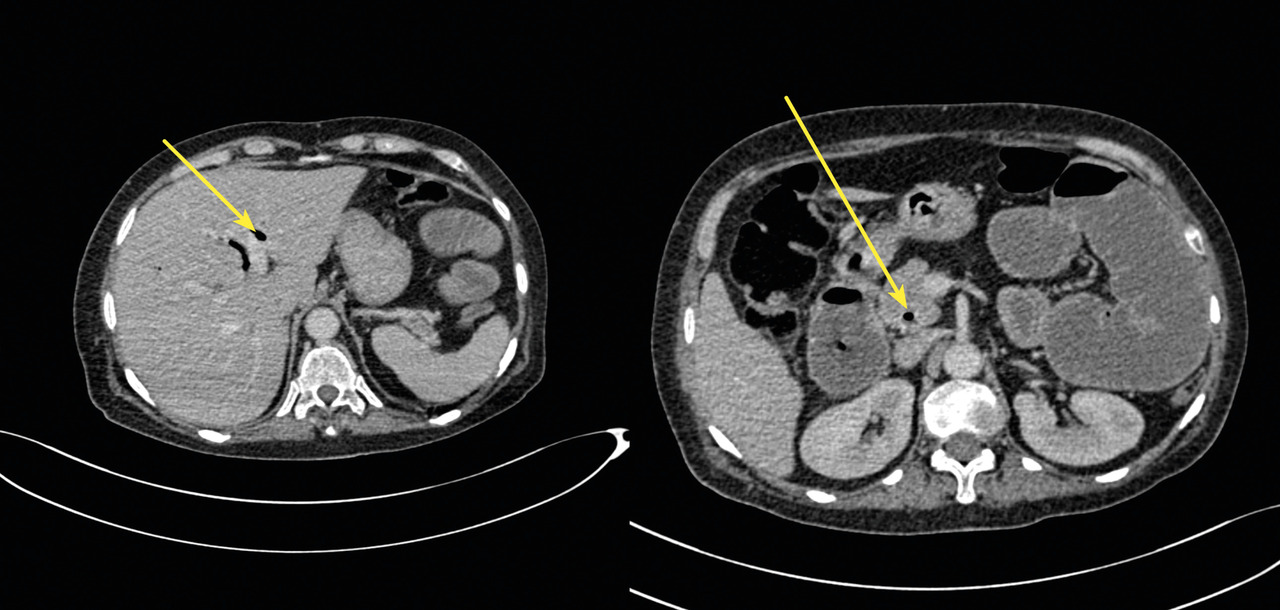

- une vésicule biliaire collabée, avec des bulles d’air (fig. 2) ;

- un trajet fistuleux entre la vésicule biliaire et le deuxième segment duodénal (fig. 2).